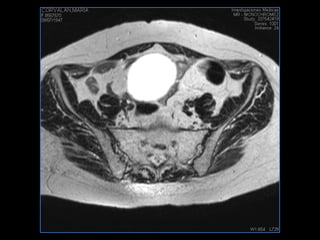

PROTOCOLO pelvis SAG T2, Y FAT SAT (FINOS) AXIAL T1  AX FAT SAT CON   GADOLINIO :  AX T1 Y COR T1 SAT: NO  FASE: RL THK: 3MM  COIL:  GAP: (FACTOR 1.4) 1MM FOV: 40 CM NEX:2 SINCRONIZACION RESPIRATORIA EN 3 O 4 CICLOS ALE